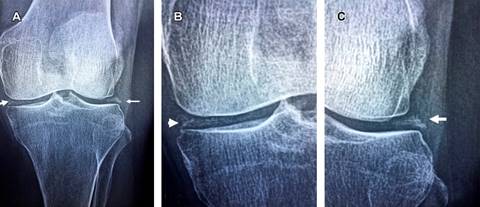

Paciente femenino de 72 años de edad, hipertensa de cuatro años de evolución. Acude a consulta con diagnóstico de gonartrosis; manifiesta dolor en rodilla izquierda de dos meses, sin mejoría al tratamiento con antiinflamatorios no esteroideos (AINE). Además, reportó la presencia de náuseas frecuentes, reflujo gastroesofágico y estreñimiento de ocho meses de evolución. A la exploración física: peso de 67 kilogramos, talla 1.60 metros, índice de masa corporal 26.2, frecuencia cardiaca 80 latidos por minuto, tensión arterial 160/90 mmHg; marcha claudicante por dolor en rodilla izquierda, con arcos de movimiento limitados a la flexoextensión en los últimos 10o y presencia de sensación de frote al desplazamiento de rótula. Valgo de rodilla izquierda de 16o, pruebas de Apley negativas, signos de cajón ausentes, fuerza muscular de cuádriceps izquierdo en 4/5 en escala de Daniels. Resto de exploración normal. Las radiografías simples de rodilla izquierda mostraron: desviación lateral de rótula, y condrocalcinosis de ambos meniscos, sin disminución del espacio articular, sin geodas ni osteofitos (Figura 1). Los estudios de laboratorio reportaron calcio sérico 11.1 mg/dL, calcio iónico 5.9 mg/dL, magnesio 2.0 mg/dL, fósforo 3.5 mg/dL, calcio en orina de 24 horas 390 mg; PTH 75.8 pg/mL. La citometría hemática, glucosa, urea, ácido úrico y perfil tiroideo se reportaron normales. Se realizó diagnóstico de condrocalcinosis meniscal e hiperparatiroidismo primario. Se solicitó gammagrafía de paratiroides con Tc99m-MIBI, la cual confirmó adenoma paratiroideo en lóbulo tiroideo inferior derecho (Figura 2A).

Figura 1: A) Radiografía simple anteroposterior de rodilla izquierda; se observa calcificación lineal de ambos meniscos, sin presencia de disminución de espacio articular, geodas ni osteofitos marginales. B y C) Acercamientos.